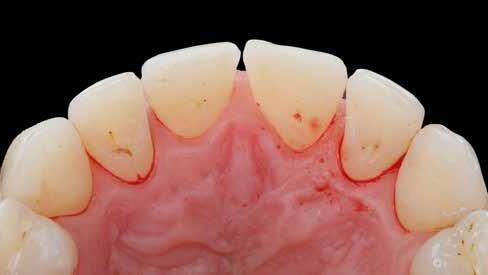

Egy 34 éves páciens esztétikai problémával érkezett. A természetesen keskeny metszőfogak miatt kisebb diasztémák és fekete háromszögek voltak láthatók a front régióban. A rések korábban kompozittal történő zárása már megtörtént, azonban az eredmény nem felelt meg az elvárásoknak (1. ábra). A fekete háromszögek továbbra is láthatóak voltak, és a kompozitanyag jól kivehetően helyezkedett el a fogak felszínén. A 11-es és 21-es fogak szélessége között aszimmetria mutatkozott, a korábbi restaurációk nehezen tisztíthatók voltak, és gyorsan elszíneződtek (2. ábra). A frontfogak palatinális felszínén retenciós drót volt rögzítve, a 11-es és 21-es fogak pedig kompozittal történő sínnel voltak összekötve (3. ábra). Bármilyen további kezelés során a retenciós drót eltávolítása szükséges, mivel az akadályozza a megfelelő approximális restaurációk kivitelezését. Az első konzultáció során teljes fotódokumentáció készült. Egy gyors kompozit mock-up segítségével bemutatásra kerültek a lehetséges esztétikai eredmények. A kezelési terv elfogadását követően időpont egyeztetésre került sor a beavatkozás elvégzésére.

1. ábra: A mosolyról készült fénykép a kezdeti vizsgálat során.

3. ábra: A 11-es és 21-es fogakat kompozittal ragasztották össze a retenciós drót felett.

A kezelés első lépése a színárnyalat kiválasztása volt. A megfelelő integráció megítélése érdekében többféle kompozitárnyalat került felhelyezésre a fogak felszínére. A GC G-ænial A’CHORD anyagból az A2, A1, JE és AE árnyalatok kerültek tesztelésre (4. ábra). Keresztpolarizációs fotó segítségével, amely kiszűri a vakuvillanás tükröződését, a színértékelés még pontosabban elvégezhető (5. ábra). Diasztémák vagy fekete háromszögek zárása során gyakran elegendő egyetlen árnyalat alkalmazása, összetett rétegzési technika nélkül. Ebben az esetben a GC G-ænial A’CHORD A1 árnyalata bizonyult a legmegfelelőbb választásnak.

Eltávolításra került a retenciós drót, valamint az összes korábbi kompozit restauráció (6–9. ábra). Ezt követően kofferdam izolálást alkalmaztunk (Isodam Heavy, Sigma Dental) a 15-östől a 25-ös fogig, majd PTFE fonalból készült ligatúrákat (Tandex) helyeztünk be az íny hatékonyabb retrakciója érdekében (10. ábra). A 13-as fognál egy további kofferdam kapocs (Brinker B4, Coltene) is felhelyezésre került, hogy fokozott retrakciót biztosítson, és megfelelően izolálja az ínyrecessziót. A kapocs ívét önsavazó folyékony kompozit-